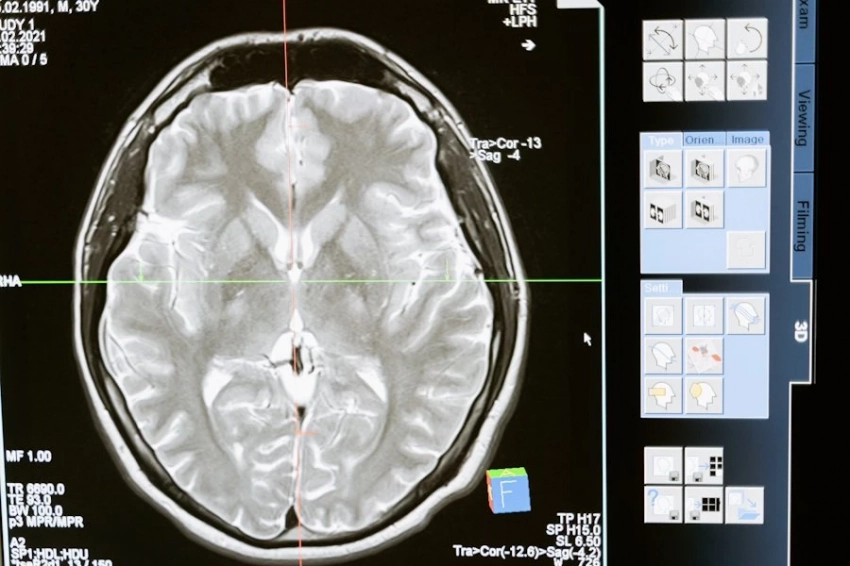

Болезнь, ставшая известной благодаря психиатру Алоису Альцгеймеру, носит его имя и представляет собой поражение мозга, при котором пациент утрачивает способность к нормальному воспоминанию. Еще совсем недавно это заболевание было характерным для пожилых людей, старше 65 лет, но последние исследования показывают, что болезнь значительно «помолодела». Уже люди сорока лет находятся в зоне риска.

Другие ученые выдвигают гипотезу, согласно которой накопление амилоидных пептидов в мозге становится основным двигателем болезни. Эти пептиды должны защищать нейроны, однако, из-за нарушения их утилизации, они начинают накапливаться, вызывая развитие болезни Альцгеймера.

Третья гипотеза сосредоточена на роли тау-белков, которые при нарушении своей структуры образуют клубки внутри нервных клеток. Эти клубки мешают нормальной передаче сигналов между клетками и могут привести к их гибели, что, в свою очередь, способствует прогрессированию заболевания.